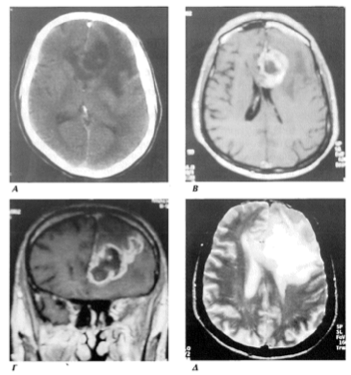

Εικόνα 8. Γλοιοβλάστωμα δεξιού μετωπιαίου λοβου. Απεικόνιση σε εγκάρσια τομή πριν χορηγηθεί παραμαγνητική ουσία (Α) και μετά την χορήγηση (Β), σε στεφανιαία τομη (Γ) και σε εγκάρσια τομή Τ2 που απεικονίζει το έντονο οίδημα (Δ).